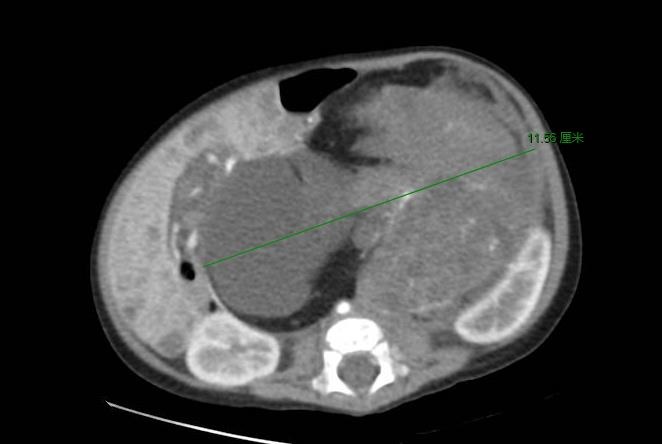

病例2:航航,5月,因洗澡时发现腹部膨隆就诊于我院,辅助检查发现腹盆腔巨大肿瘤占位,行腹膜后肿瘤切除术,完整切除肿瘤,术后病理报告示:1级未成熟型畸胎瘤,恢复顺利,建议密切随访复查。

航航肿瘤CT照片